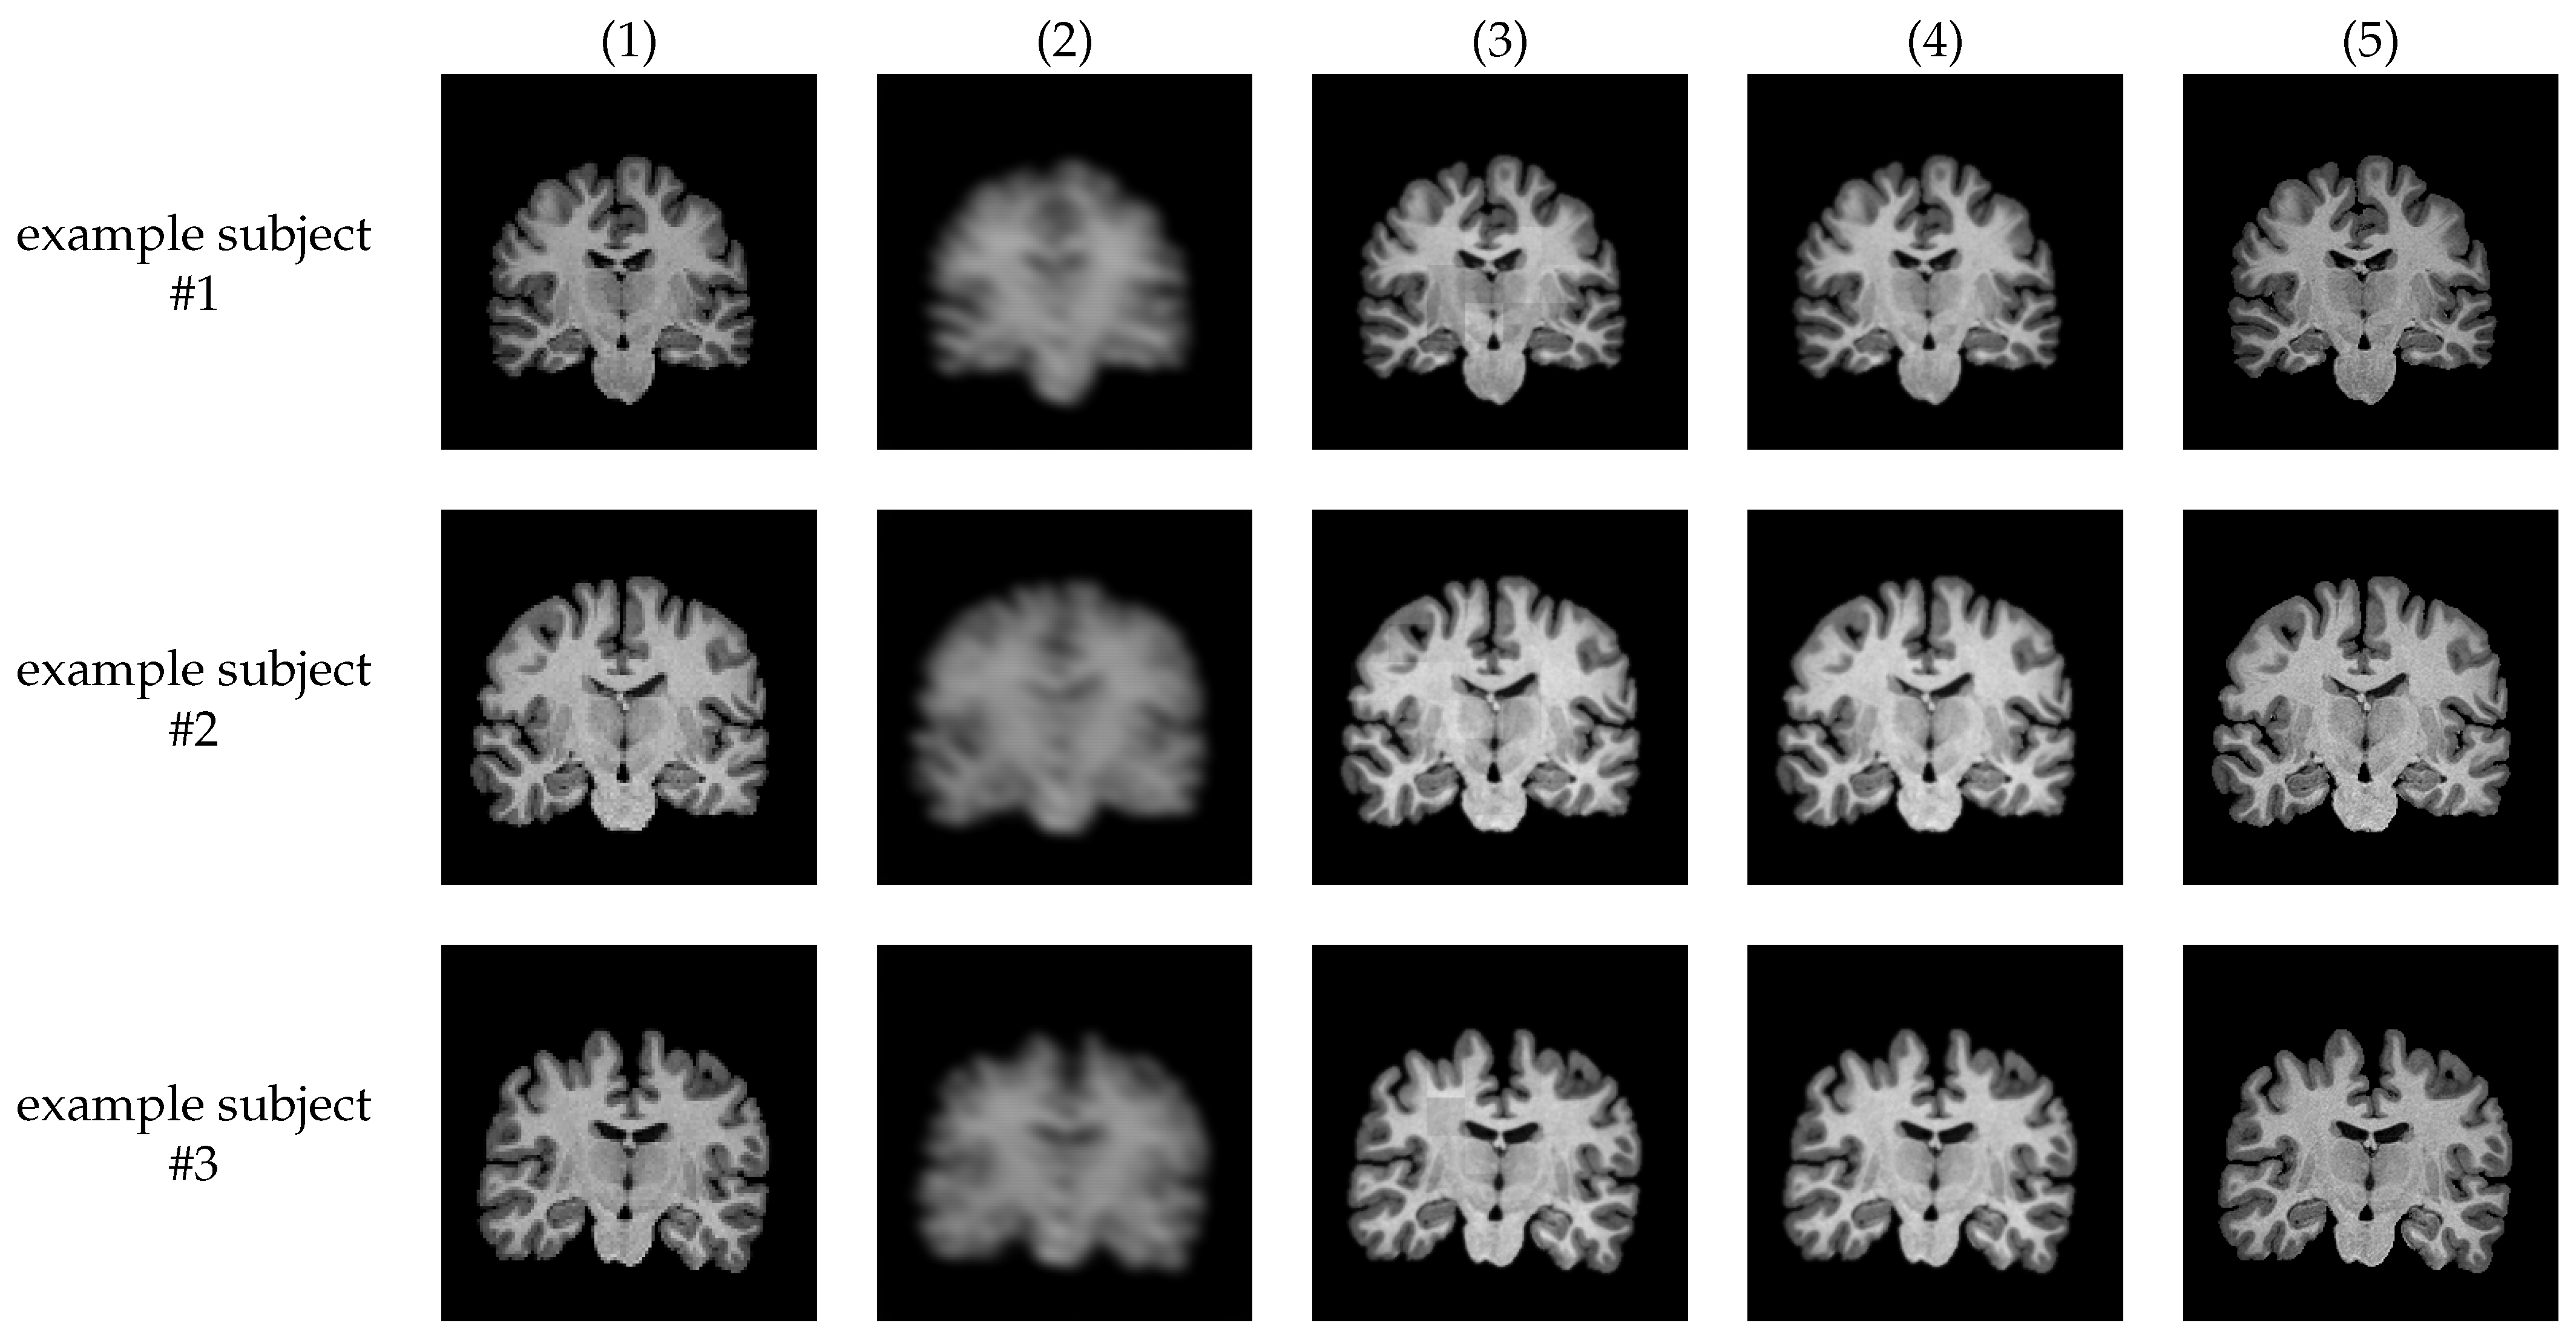

Figure 2 and Figure 3 show examples of MR images generated by proposed super-resolution networks and their original HR images, and their magnified view, respectively. In Table 1, the average SSIM and PSNR between super-resolved images using each method and their ground-truth high-resolution images are also summarized.

Figure 2.

Examples of generated images with their input and ground-truth images. (1) low-resolution input image, (2) ESRGAN without SPS and ASD, (3) ESRGAN + SPS, (4) ESRGAN + SPS + ASD (proposed), and (5) ground truth high-resolution image.

Figure 3.

Magnified example of the the generated image.

The output images of the network without SPS, i.e., plain ESRGAN (column (2)), are visibly blurry, and most of the structural features are lost, leading to the lower SSIM/PSNR value. With the proposed SPS (column (3)), generated images are significantly sharper and visibly natural-looking. However, grid-shaped intensity shifts appear at the joints of each patch (Figure 3 (3)). On the other hand, almost all the intensity shifts are suppressed with the images with the proposed discriminator (column (4)).